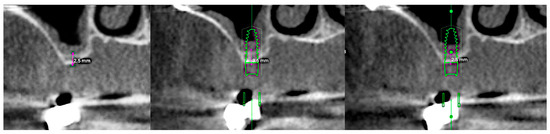

2. Case Presentation

- A 2.2 mm twist drill was used at site 1.6 with a 2 mm stopper (1 mm shorter than the 3.6 mm bone height) at the same speed.

- A 2.8 mm CAS drill, with rounded apical geometry to minimize the risk of Schneiderian membrane perforation, was used with a 3 mm stopper at 400–800 rpm [13].

- A sinus probe with a 4 mm stopper confirmed bone presence at the base of the osteotomy. The same stopper was then used with the 2.8 mm drill to extend preparation by 1 mm.

- A probe with a 5 mm stopper confirmed sinus floor preparation and membrane integrity. A Valsalva maneuver also confirmed the absence of perforation.

- A 3.1 mm CAS drill was then used with the final stopper to slightly widen the implant site, creating under-preparation for better implant stability.

- Hydraulic membrane elevation was performed using sterile saline, infused gradually in 0.5 cc increments to a total of 2.0 cc across both sites.

- At site 1.7, CAS drills (2.8 mm and 3.1 mm) with 3 mm stoppers were used, and an additional 1.0 cc of saline was infused for complete sinus membrane detachment. The first implant site was sealed to prevent saline leakage.